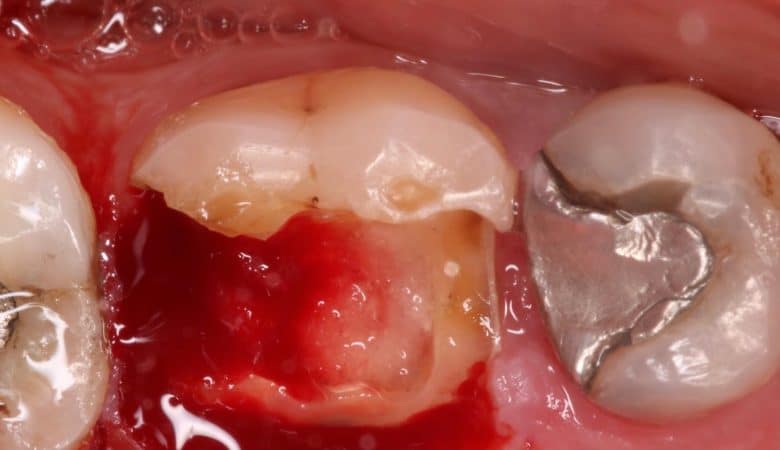

The case presented below is for a 28 year-old female patient. She had multiple spacing in her maxillary anterior segment. The treatment options for such case would be orthodontic treatment (i.e., which is the ideal treatment option), indirect restorative approach,…